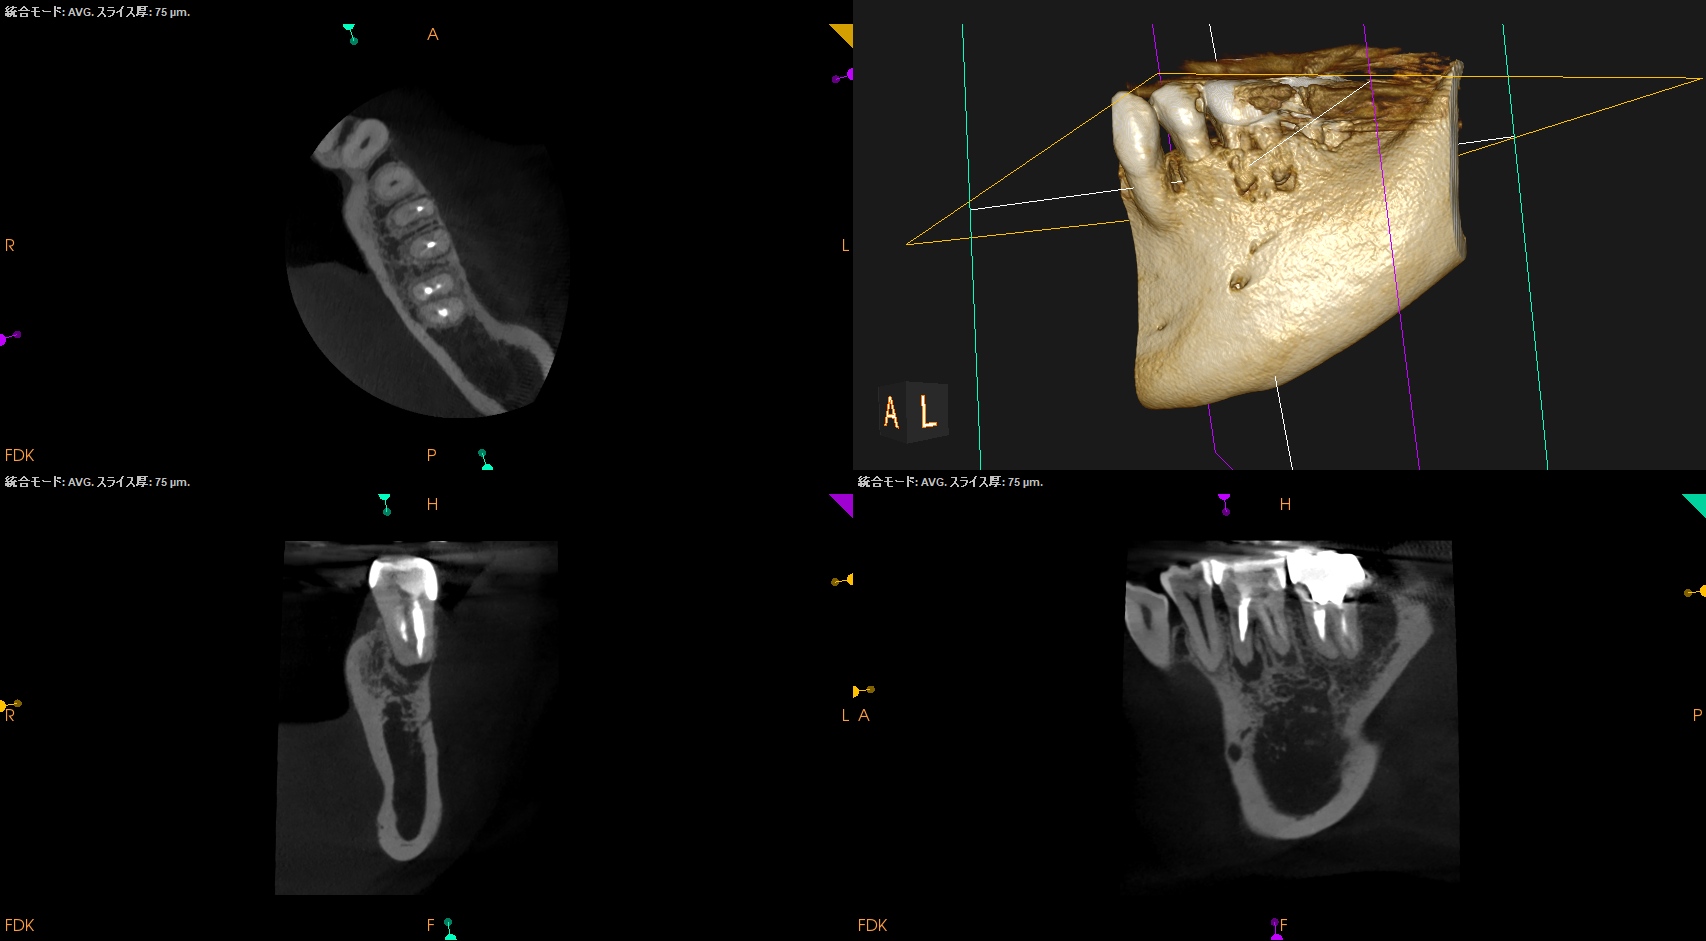

CBCT(2025.9.16)

MB

ML

D

MにもDにも病変がある。

B

頬側の骨がない。

これが圧痛に対する反応の原因だ。